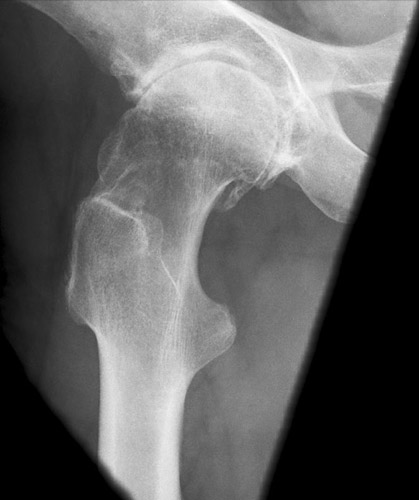

Der distale Schenkelhalsteil wird durch den Trochanter major verdeckt, wobei aber der mediale gelegene Abschnitt relativ frei ist. Außerdem ragt der Trochanter minor besonders markant und in ganzer Ausdehnung hervor und projiziert sich weit distal vom Trochanter major. Diese Fehleinstellung kommt vor allem bei Menschen mit schweren arthrotischen Knochenwülsten (Coxarthrosis deformans) am Hüftgelenk vor.

Der Patient konnte zwar seinen Oberschenkel abspreizen, aber offenbar nur ungenügend; er drehte daher das Bein stark nach außen, was den Trochanter minor auf dem Bild mächtig hervorragen ließ.